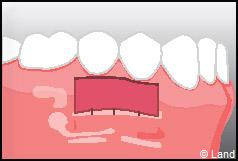

LES TECHNIQUES SANS APPORT DE GENCIVE :

Elles font appel à des lambeaux de gencive restante à proximité des récessions, qui sont déplacés et repositionnés sur la récession.

Dans ce cas le lambeau est déplacé latéralement pour combler la récession.